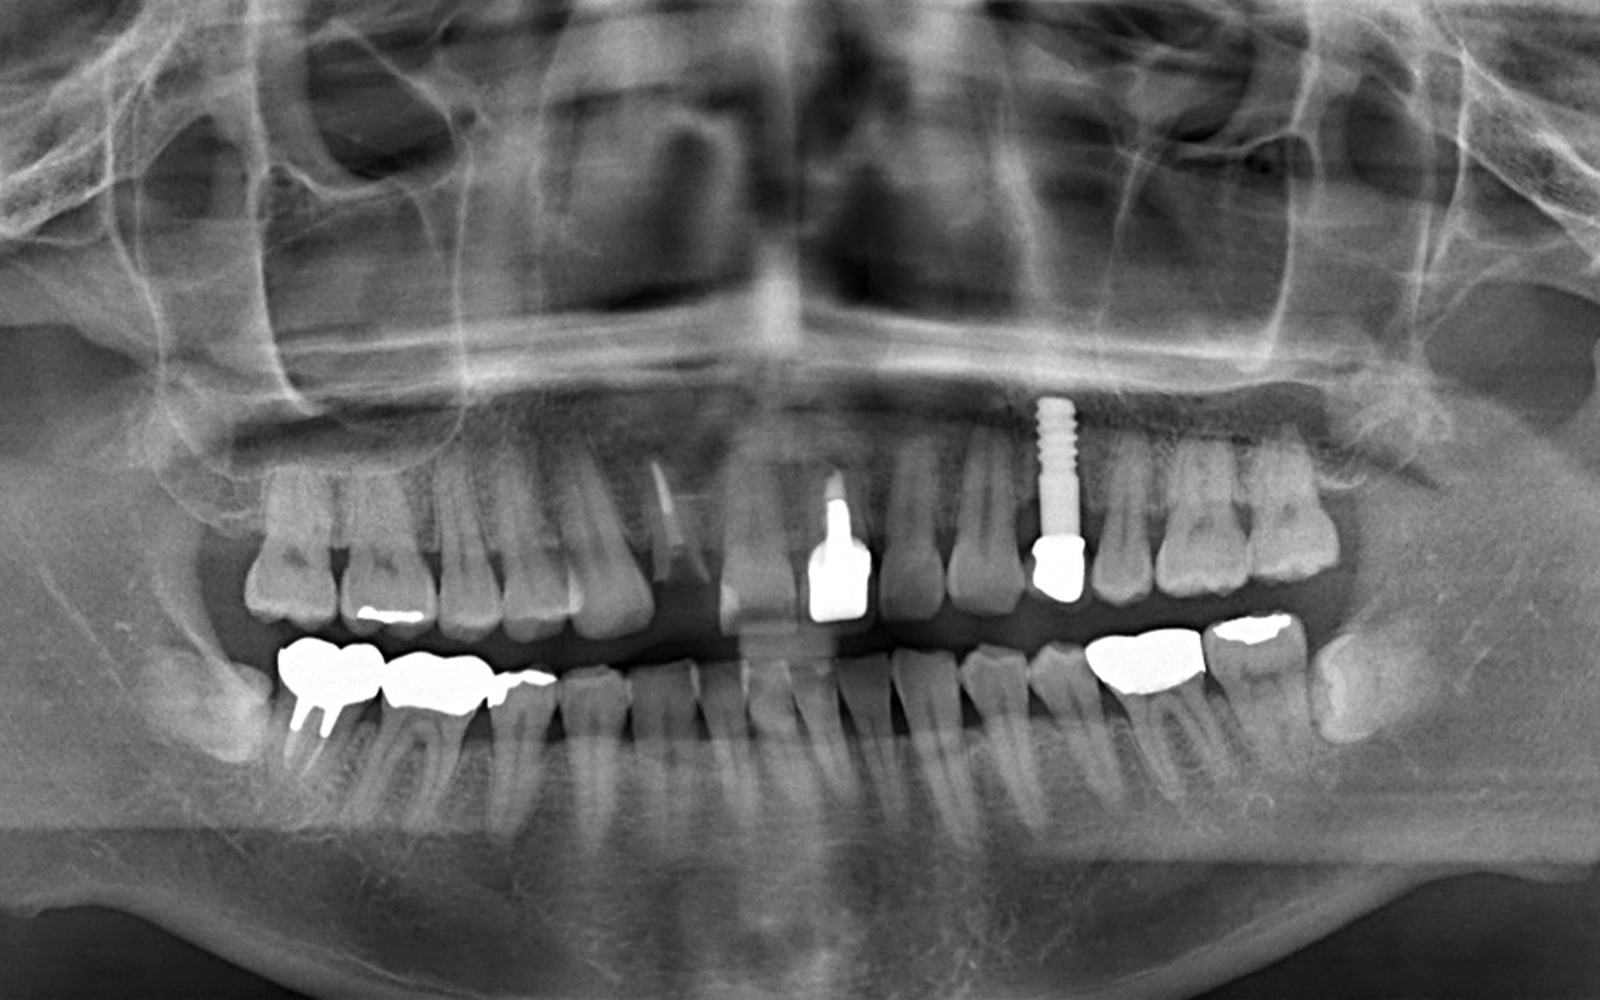

レントゲン写真でも、前歯部(右上2番・左上1番)の歯根周囲の状態から、これらの歯を保存することが難しいと判断しました。

レントゲン写真では、当院で治療した「2本のインプラント体」が骨の中にしっかりと埋入されていることが確認できます。(*治療前のレントゲン写真を見るとわかる通り、当院で治療する前から1本インプラントが入っていたので、治療後は合計3本のインプラントが埋め込まれていることになります。)

そして、インプラント(写真内に写っている白いネジ状の物体)の周囲に骨が十分に存在しており、骨吸収(骨が溶けて減ること)は認められません。

抜歯と同時に埋入を行ったにもかかわらず、周囲の骨がしっかりと保たれていることは、抜歯即時埋入の大きな利点です。